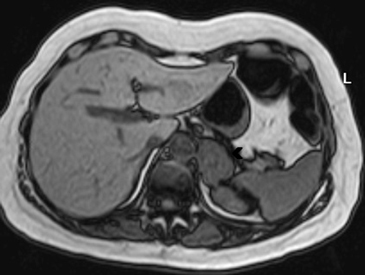

En la TC no contrastada las glándulas suprarrenales normales son homogéneas y simétricas, con una densidad muy similar a la del parénquima renal adyacente (Figura 1 a). Con un medio de contraste ev la glándula suprarrenal se opacifica en forma homogénea, similar al hígado o al bazo (Figura 1 b). Si la cantidad de tejido adiposo retroperitoneal es abundante las glándulas suprarrenales pueden aparecer enteramente rodeadas por grasa y su delimitación es más fácil (Figura 2 a); lo inverso ocurre en pacientes muy delgados con escasa grasa retroperitoneal (Figura 2 b). En RM, en secuencias ponderadas en T1 y T2 convencionales tienen una intensidad de señal homogénea, hipointensa respecto de la grasa adyacente e iso o hipointensa con respecto del parénquima hepático (Figura 3 a y b). En los cortes coronales se aprecia mejor la forma y la posición de las glándulas suprarrenales (Figura 3 c).

Figura 3. Glándula suprarrenal normal en resonancia magnética. (a) Cortes axial ponderado en T1 la señal de la glándula normal (flecha negra) es hipointensa respecto a la grasa retroperitoneal e isointensa respecto al parénquima hepático. (b) Cortes axial ponderado en T2 en que se muestra la glándula suprarrenal derecha (flecha blanca) y (c) corte coronal ponderado en T2 en que se muestra la glándula suprarrenal derecha (flecha blanca) y la glándula suprarrenal izquierda (flecha negra) con similares características de intendidad de señal. 3. Causas y prevalencia de las lesiones suprarrenales